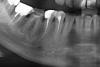

Olga55 Опубликовано 4 февраля, 2013 Поделиться Опубликовано 4 февраля, 2013 Доброго времени суток, уважаемые доктора! Обращаюсь к вам за помощью. 24/01 сего года мне залечили пульпитный зуб, 5-ка снизу справа: вскрыли канал, удалили нерв, прочистили, запломбировали гуттаперчей (извиняюсь, если не правильно написала), поставили штифт и большую пломбу. Предварительно была сделана анестезия, укол был очень больным, но практически не подействовал, и потому поставили дополнительную анестезию плюс укол в нерв. В этот день зуб чувствовал себя прекрасно. Следующие 2 дня ныл. На 3-й день вообще разболелся. И слегка опухла щека. А в том месте, где, по всей видимости, была поставлена анестезия, со стороны щеки я нащупала небольшое уплотнение в десне (приблизительно 5х5 мм.) На 4-й день я пошла к врачу. Мы сделали снимок. На снимке всё было хорошо. Но посоветовали попить для профилактики или антибиотики, или "Найз". Я сказала, что пить всё это скорее всего не буду, потому как в данный момент пролечиваю обострение ЖКТ-проблем, и антибиотики с "Найзом" будут совсем не кстати! Мне сказали, что без лекарств это рассосётся, но подольше. Предложили ещё сделать разрез в десне. На 7-й день, так как зубное нытьё продолжалось, я всё-таки пошла на консультацию к хирургу. Все эти дни зуб умеренно, но неприятно ныл. И при надкусывании по-прежнему было больно. Мы сделали общий снимок всей челюсти. И он, пощупав десну, сказал, что резать тут нечего. Но про антибиотики тоже упомянул, но как-то не настойчиво. Есть предположение, что припухлость и небольшое уплотнение - это гематома после анестезии. Сегодня идёт 11-й день после лечения. Щека всё ещё слегка опухшая (в принципе, практически незаметно). Но небольшое уплотнение остаётся, и у оснований зубов: с 4-го по 7-й нижние справа (где залеченный зуб) есть синеватая каёмка на десне (это может быть признаком гематомы?). И зуб продолжает ныть, то меньше, то больше. При надкусывании всё так же некомфортно. И никакой динамики я не вижу, ни в ту, ни в другую сторону... Температуры особой эти дни не было. Только пару раз - слегка за 37. Хотя, я иногда меряю по несколько раз в день. Подскажите пожалуйста, может ли зуб так долго ныть (уже 11-й день со дня лечения), потому что гематома и потому что канал запломбирован очень глубоко? Но это всего лишь мои предположения... И что за тёмное пятнышко в десне под залеченным зубом (обвела его красным)? Может, мне попали куда-то в нерв? Потому что иногда ощущение, что немеют нижние передние зубы или подбородок. (Возможно, это кажется.) Насколько оправданы здесь антибиотики? Если даже толком никто не сказал, в чём же причина болезненности зуба без нерва. Ссылка на комментарий